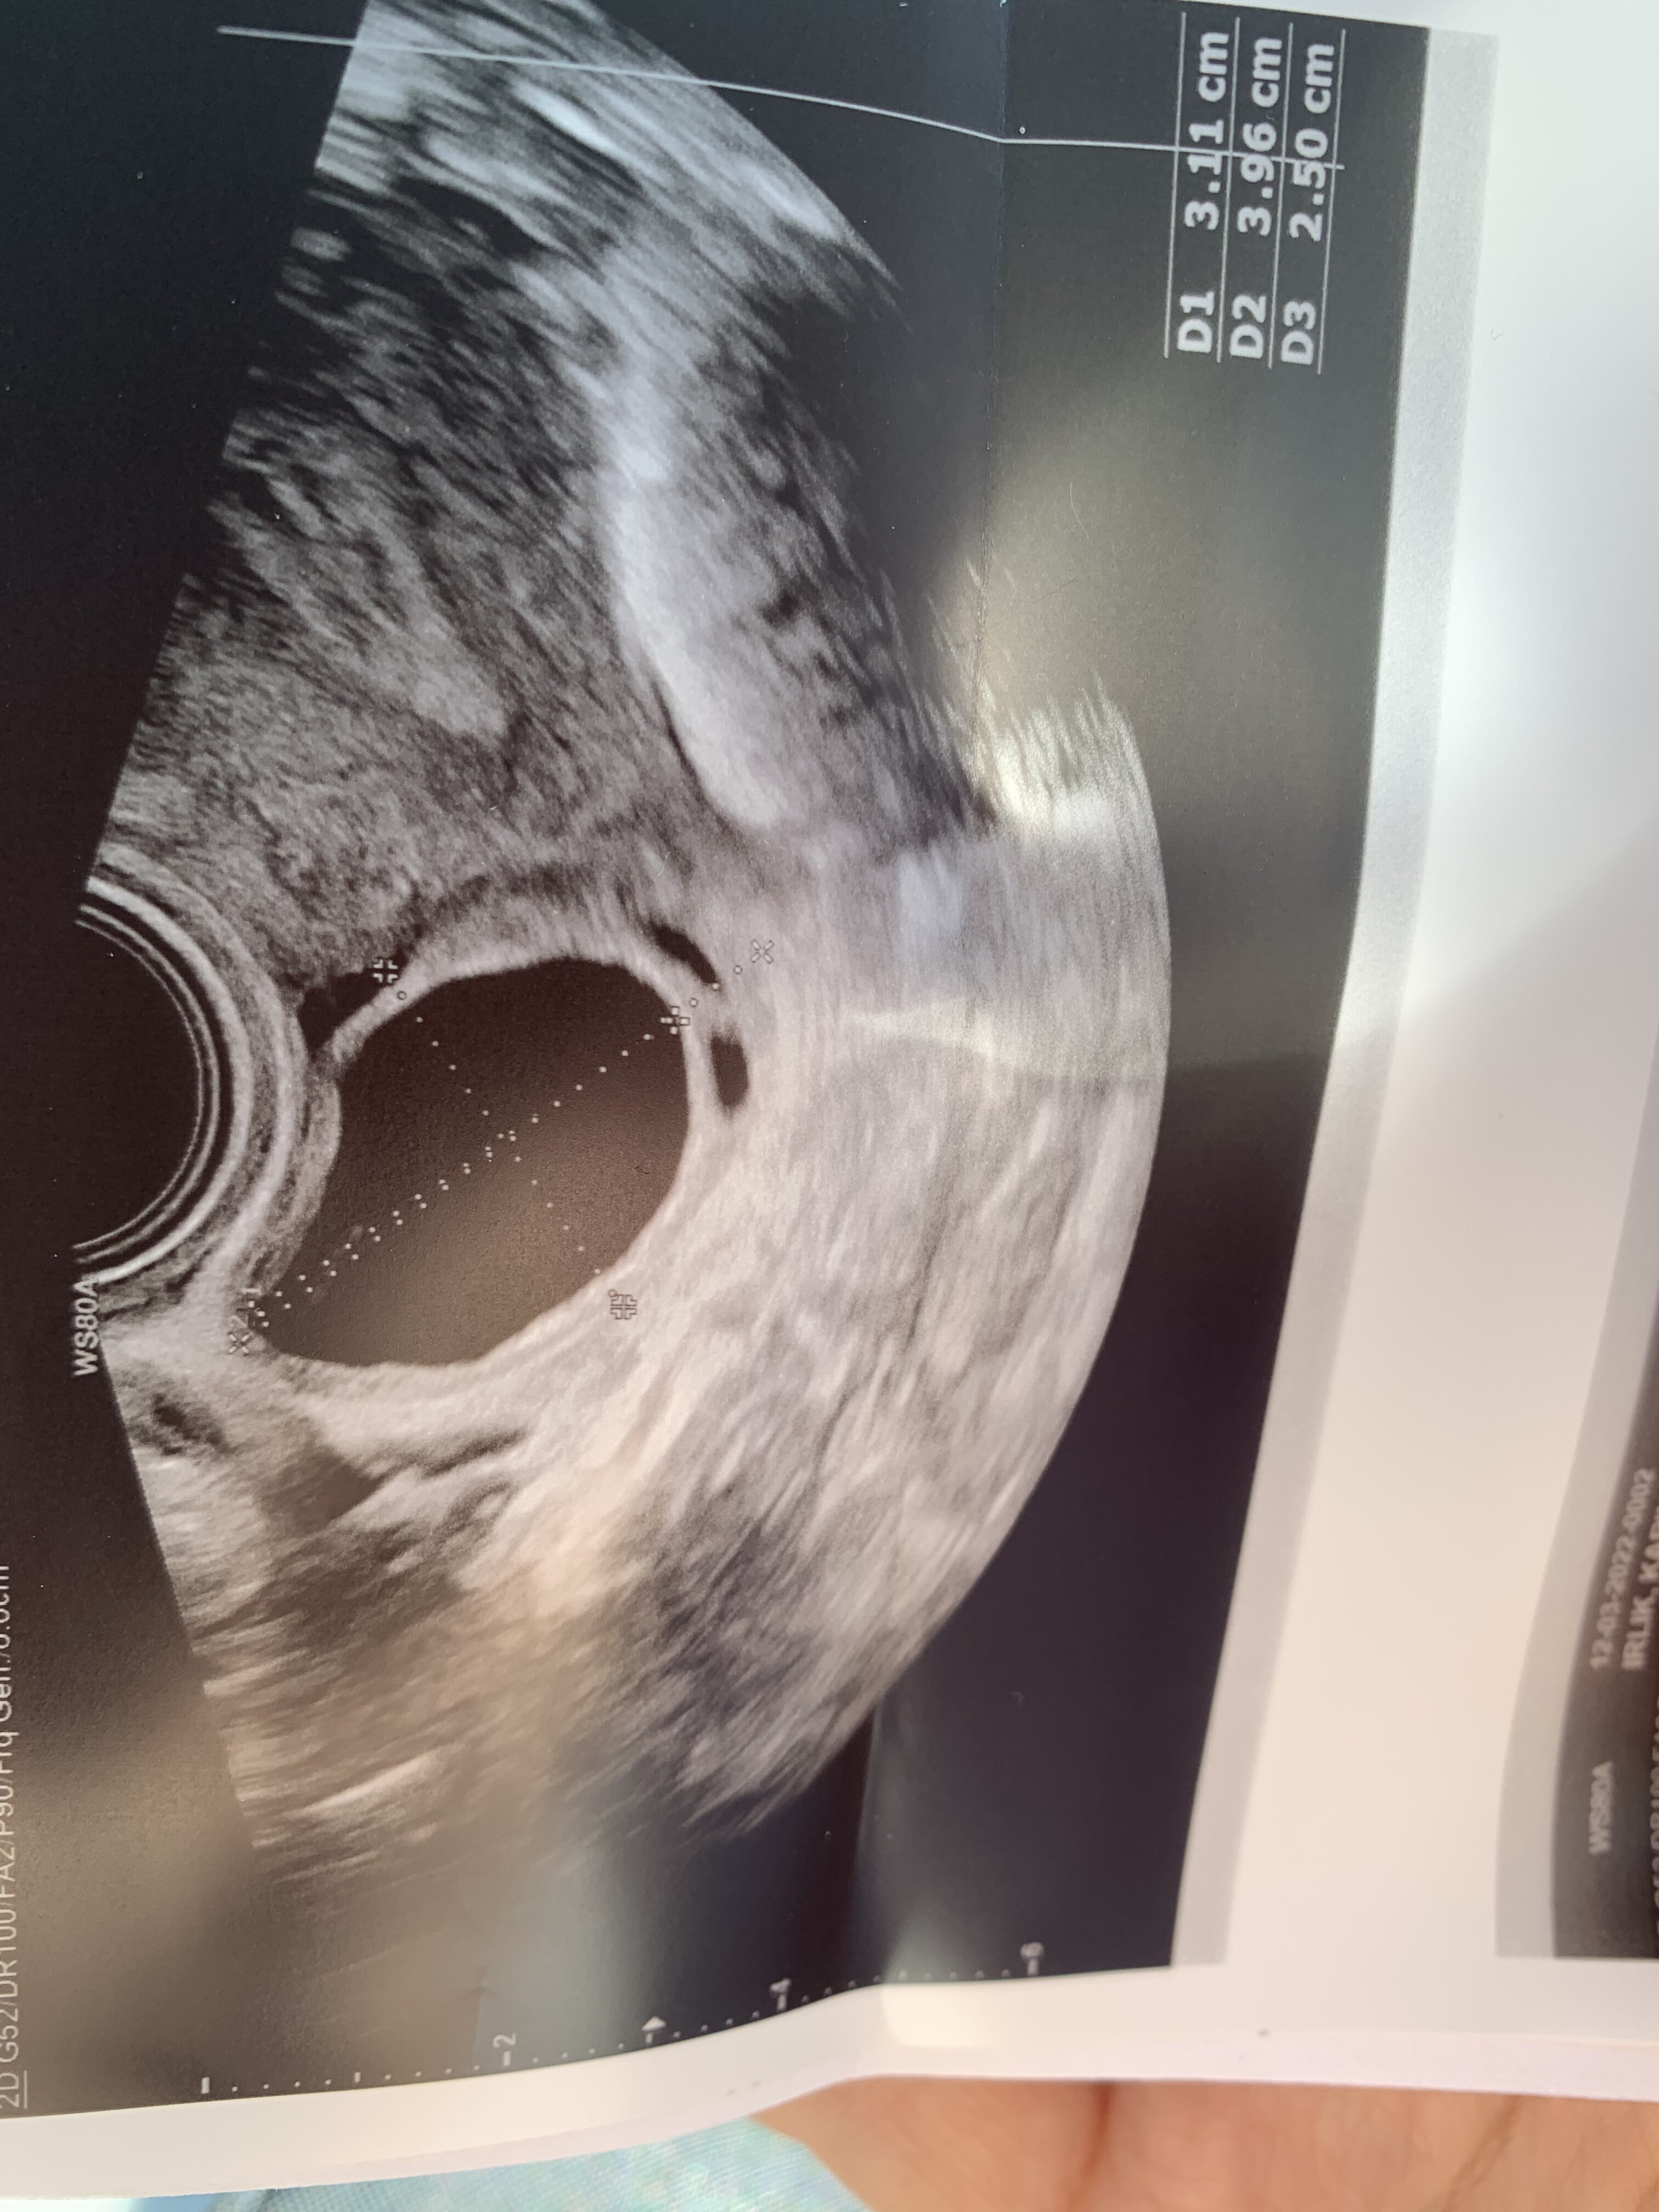

No faktycznie pecherzyk już trochę przestarzały… ale to, ze tylko jeden to akurat dobra informacja, bo wielu ginekologów przy dwóch i więcej nie chce dawać zastrzyków ze względu na ryzyko ciąży mnogiej.Zobacz załącznik 1378522Zobacz załącznik 1378523

Clo od 3 do 7dc. Dziś 12dc/27, pęcherzyk 31mm, endo 9mm. Nie dostałam nic na pęknięcie, bo już zaczyna się pojawiać płyn w zatoce. Ale chyba za duży urosnął ten pęcherzykno i znowu tylko jeden. Dr powiedziała, że jak mam męża w domu to po powrocie żeby go wziąć w obroty, a stary z tego wszystkiego chyba za bardzo się zestresował i nie dał rady

Ależ jestem wściekła na swój organizm. Termin owu mi wypada teoretycznie w poniedziałek, testy owu bladziutkie były dotychczas. Myślałam, że będzie więcej tych pęcherzyków, że chociaż jeden będzie miał kilkanaście mm, że zastrzyk dostanę na pękanie,a tu nie dość, że 30mm to jeszcze to endo 9mm. Chyba trochę za słabo, nie?No faktycznie pecherzyk już trochę przestarzały… ale to, ze tylko jeden to akurat dobra informacja, bo wielu ginekologów przy dwóch i więcej nie chce dawać zastrzyków ze względu na ryzyko ciąży mnogiej.

Co do testów owu to ja właśnie dziś się dowiedziałam, że miałam owulację w dniu w którym wyszedł mi pierwszy pozytywny test - testy robiłam co 4h od rana, pozytywny był dopiero o 22.00 w czwartek a według gin w czwartek musiała być owu. Więc nawet jeśli testy są nadal negatywne to owulacja spokojnie może wystąpić.Ależ jestem wściekła na swój organizm. Termin owu mi wypada teoretycznie w poniedziałek, testy owu bladziutkie były dotychczas. Myślałam, że będzie więcej tych pęcherzyków, że chociaż jeden będzie miał kilkanaście mm, że zastrzyk dostanę na pękanie,a tu nie dość, że 30mm to jeszcze to endo 9mm. Chyba trochę za słabo, nie?z takiego 30mm to myślicie że jakakolwiek szansa jeszcze jest? Mówiła ze już płyn jest w zatoce i zaczyna się zapadać to może jednak jest jakaś szansa

Jeśli chodzi o pęcherzyk to mi zazwyczaj pękają w okolicy 26-30mm więc jakieś szanse na pękniecie są moim zdaniem.

A endo 9mm moim zdaniem jest super- ja mam co miesiąc 7mm co jest absolutnym minimum, czasem zdarzy się 8mm.